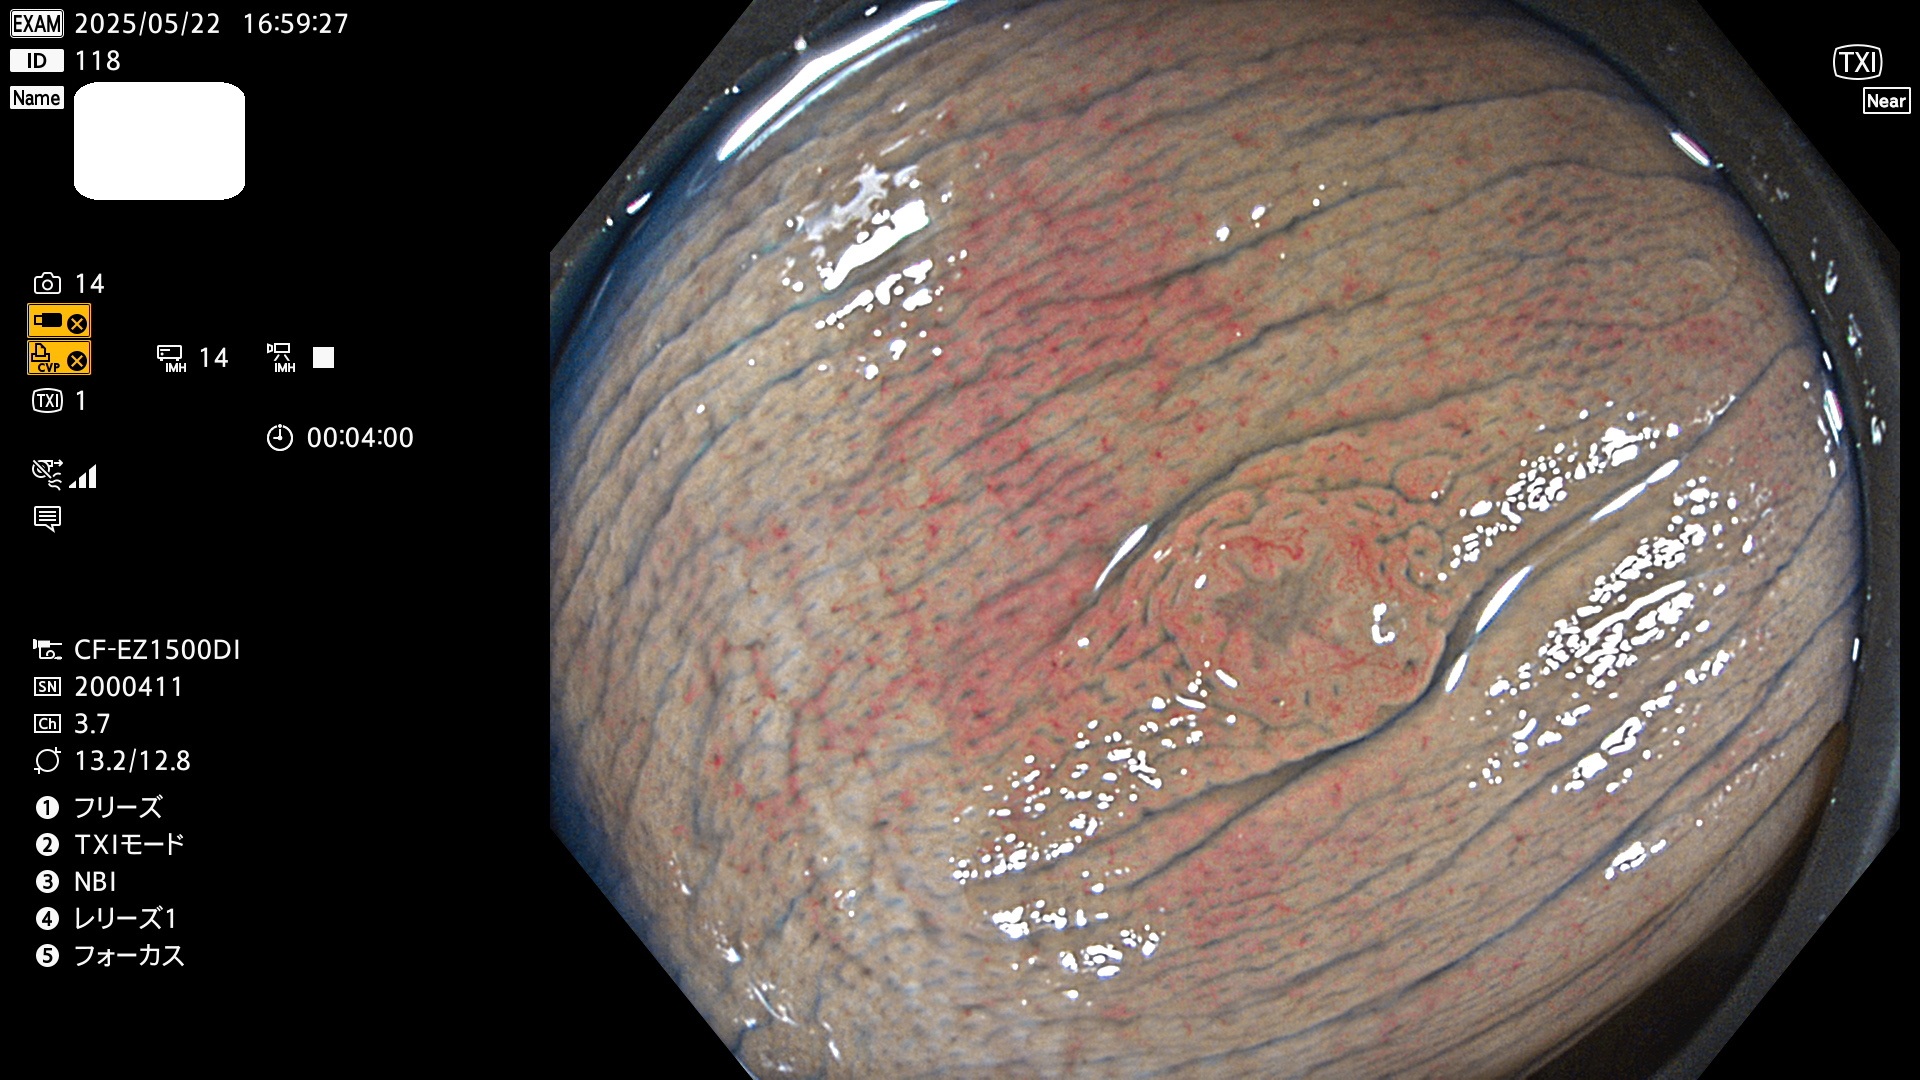

今週のUb、Uc型腺腫

完全に平坦な物をUb、陥凹している物をUcと呼びます。Ubは認識が困難で、Ucはびらん(炎症)と紛らわしいために見落とされやすく、「内視鏡後・大腸癌」の原因になります。

毎週の検査(木・金・土・日)に発見されたUb、Uc型・腺腫を、その週の日曜の夜にUPし1週間、提示します。

抽出の対象期間 2025年5月22日〜5月25日の4日間(48件の検査)10個 (10/48=21%)